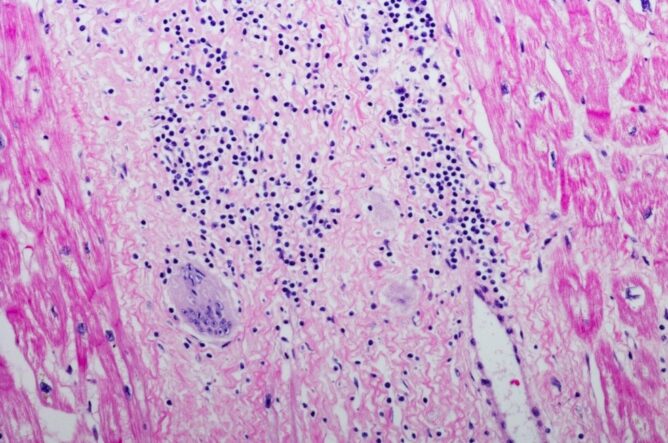

Imunski sistem je kompleksen sistem, sestavljen iz različnih tkiv, celic in molekul, ki posamezniku omogočijo zaščito pred okužbami in odziv na različne bolezni. Na splošno ga delimo na prirojeni in pridobljeni. Kako se bo odzval posameznikov imunski sistem na določen dražljaj, je odvisno od genetske zasnove, starosti, prehranskega in presnovnega ter bolezenskega stanja. Za optimalno delovanje vseh celic je potrebna ustrezna in zadostna prehrana, kar vključuje tudi celice imunskega sistema. Za samo krepitev imunskega sistema z uravnoteženo prehrano in redno telesno vadbo ni nikoli prepozno.